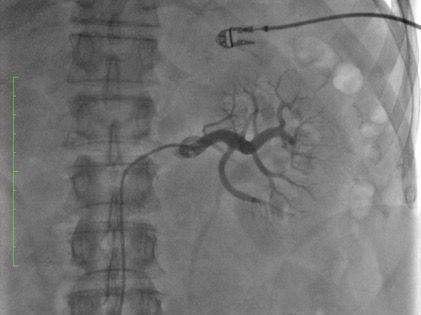

El procedimiento, según explica el doctor Rumoroso, se caracteriza por su seguridad, es mínimamente invasivo y se realiza de forma percutánea mediante el sistema Symplicity™ de Medtronic. "Introducimos un catéter por la arteria femoral y lo dirigimos hasta las arterias renales. Una vez posicionado, se aplica radiofrecuencia, generando energía térmica que neutraliza las terminaciones nerviosas simpáticas de la zona", aclara el especialista. "Los pacientes pueden regresar a casa el mismo día del procedimiento y reincorporarse a su vida diaria habitual", señala el doctor Rumoroso.